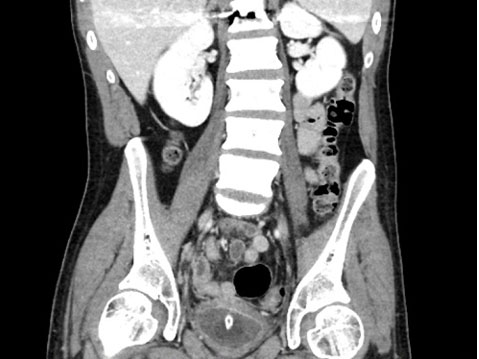

The patient is a 25-year-old man who sustained a T12 spinal cord injury July 2020 resulting in neurogenic bladder managed with self-exchanged IDC. He was previously noted at flexible cystoscopy to have a superficial false passage on the ventral surface of the penile-bulbar urethral junction. These were reported as healed at flexible cystoscopy in 2021. He first presented in April 2023 to a regional hospital complaining of a 36-hour history of decreased appetite, right iliac fossa pain, and subjective fevers. An ultrasound abdomen (Figure 1) demonstrated a small amount of free fluid in the right pelvis and a 7 mm blind ending tubular structure with surrounding hyperemia, echogenic fat, and local tenderness—felt to be in keeping with acute uncomplicated appendicitis. He subsequently proceeded to laparoscopic appendectomy and was found intraoperatively to have appendix and omentum adherent to his bladder, underneath which his IDC was seen to have eroded into the peritoneal cavity. The defect was laparoscopically repaired and patched with omentum, and an IDC reinserted. The bladder was noted to appear chronically inflamed [thickening of bladder wall noted on CT 2 months prior (Figure 2)]. He was managed post-operatively with intravenous (IV) antibiotics and discharged five days later. Computed tomography (CT) cystogram 10 days later showed no leak (Figure 3). He was discharged with an IDC at this time.

Figure 2: Image from CT abdomen and pelvis 17th February 2023 demonstrating an indwelling catheter within a thick-walled bladder.